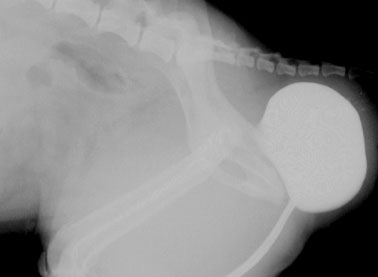

5. Treatment of genetic (congenital) problems, e.g., abdominally retained testicles (cryptorchidism). Cryptorchidism is where a male dog's testicles do not completely descend into the scrotum. Descent to the final scrotal position is complete by two months of age, otherwise, if by six months of age the testicles have not descended, they are considered to be cryptorchid or retained.